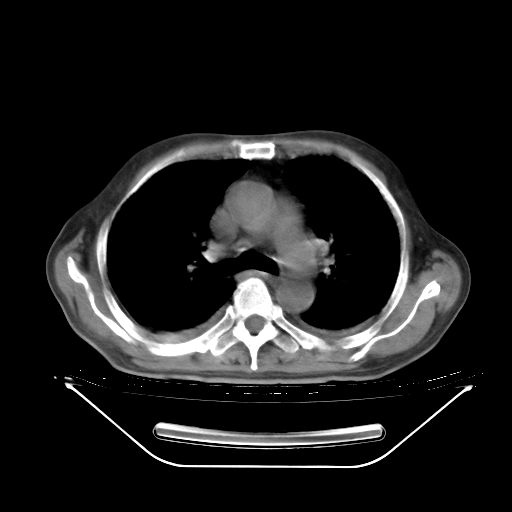

今天复查肺部CT,发现双肺广泛磨玻璃样改变。所以我把3月19日和5月9日相隔50天的肺部CT上传。请大家会诊。

2009年3月19日肺部CT片。

5月9日肺部CT(在4月27日齐鲁医院肺部CT描述部分肺组织磨玻璃样改变,12天后肺组织广泛磨玻璃样改变)